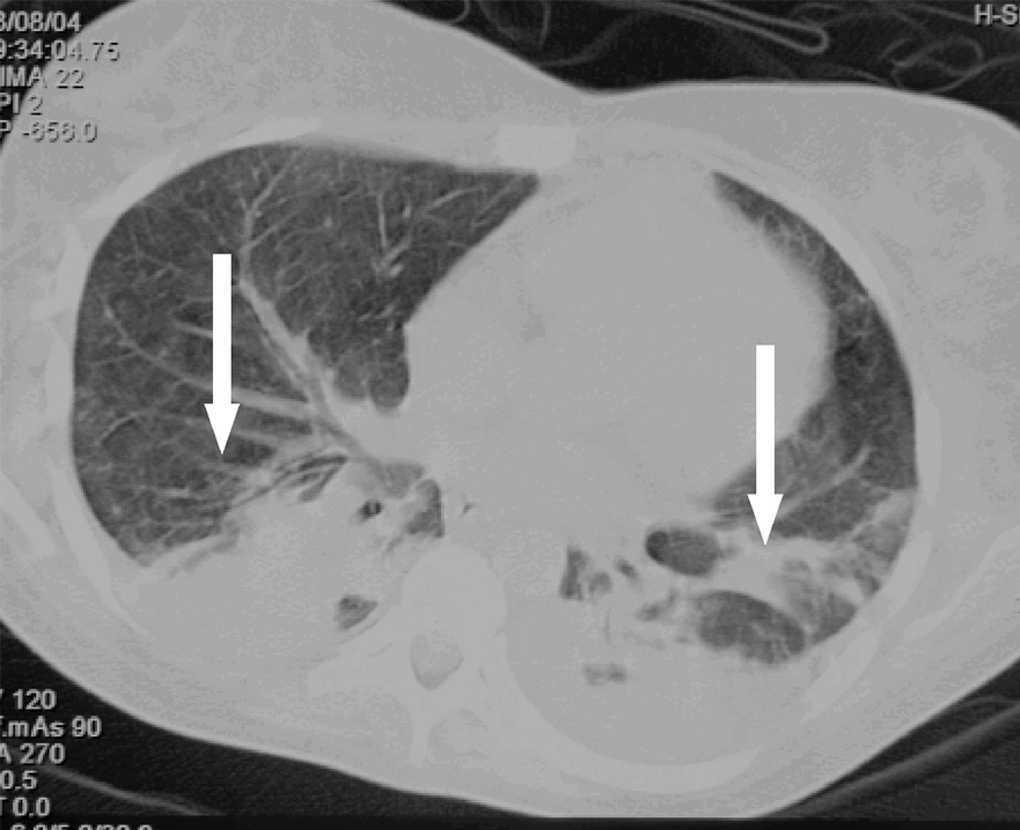

Mujer de 31 años, que ingresa por shock séptico aislándose en dos hemocultivos Staphylococcus aureus en paciente con neutropenia febril de 5 días de evolución tras ciclo de consolidación de linfoma no Hodgkin B, por lo que recibió tratamiento antibiótico empírico en un primer momento con vancomicina e imipenem y posteriormente dirigido con cloxacilina y la retirada del catéter de Hickman, cuyo cultivo semicuantitativo fue negativo. No precisó ventilación mecánica. La radiografía (Rx) de tórax fue normal. Al no encontrar foco evidente de infección se realiza tomografía axial computarizada (TAC) torácica a su ingreso que muestra mínimos cambios consistentes en engrosamiento discretamente irregular de los septos interlobulillares de ambos lóbulos inferiores en su porción posterior, diagnosticándose de neumonía (fig. 1; flechas negras). La paciente evoluciona de forma satisfactoria, desapareciendo la fiebre, pudiéndose retirar los inotrópicos y vasopresores y mejorando la relación PaO2/FiO2; recupera la neutropenia a los 10 días de ingreso en que se realiza TAC de control que confirma consolidación alveolar bilateral (fig. 2; flechas blancas).

Figura 2